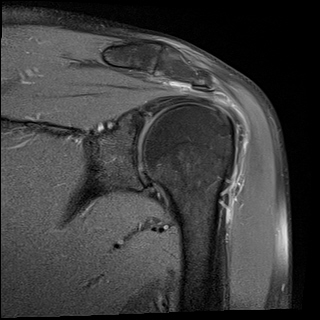

À̵ιڱ٠Ⱦ´Ü¸é°Ë»ç¿¡¼­ Á¤¸Æ³¶ÀÇ ºÎÁ¾ÀÌ °üÂûµÊ(±×¸² 1).

±Ø»ó°Ç³»Ãø Á¾´Ü¸é°Ë»ç¿¡¼­ ±Ø»ê°Ç ºÎÂøºÎÀÇ  ÀÛÀº ÆÄ¿­°ú Á¡¾×³¶ ºÎÁ¾ÀÌ °üÂûµÊ(±×¸² 2, 3).